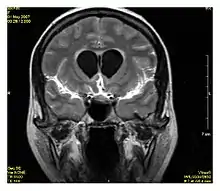

| Double inversion recovery | DIR | Simultaneous suppression of cerebrospinal fluid and white matter by two inversion times.[25] | High signal of multiple sclerosis plaques (pictured).[25] | ![]() | |